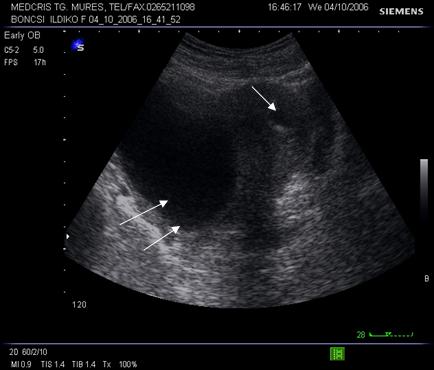

Fig nr 6 Decolare de pol inferior ( cu sageata ) la o sarcina de 7 sapt

Fig. nr. 66. Aceeasi sarcina, ca in figura precedenta, la 12 saptamani , fara imagini patologice la polul inferior ovular, marcat cu sageata

Fig nr. 67 Decolare de pol inferior ovular, situat in continuarea canalului cervical

( sageata) la ecografia transvaginala

Fig nr 68 Decolare de pol inferior la ecografia abdominala ( sageata )